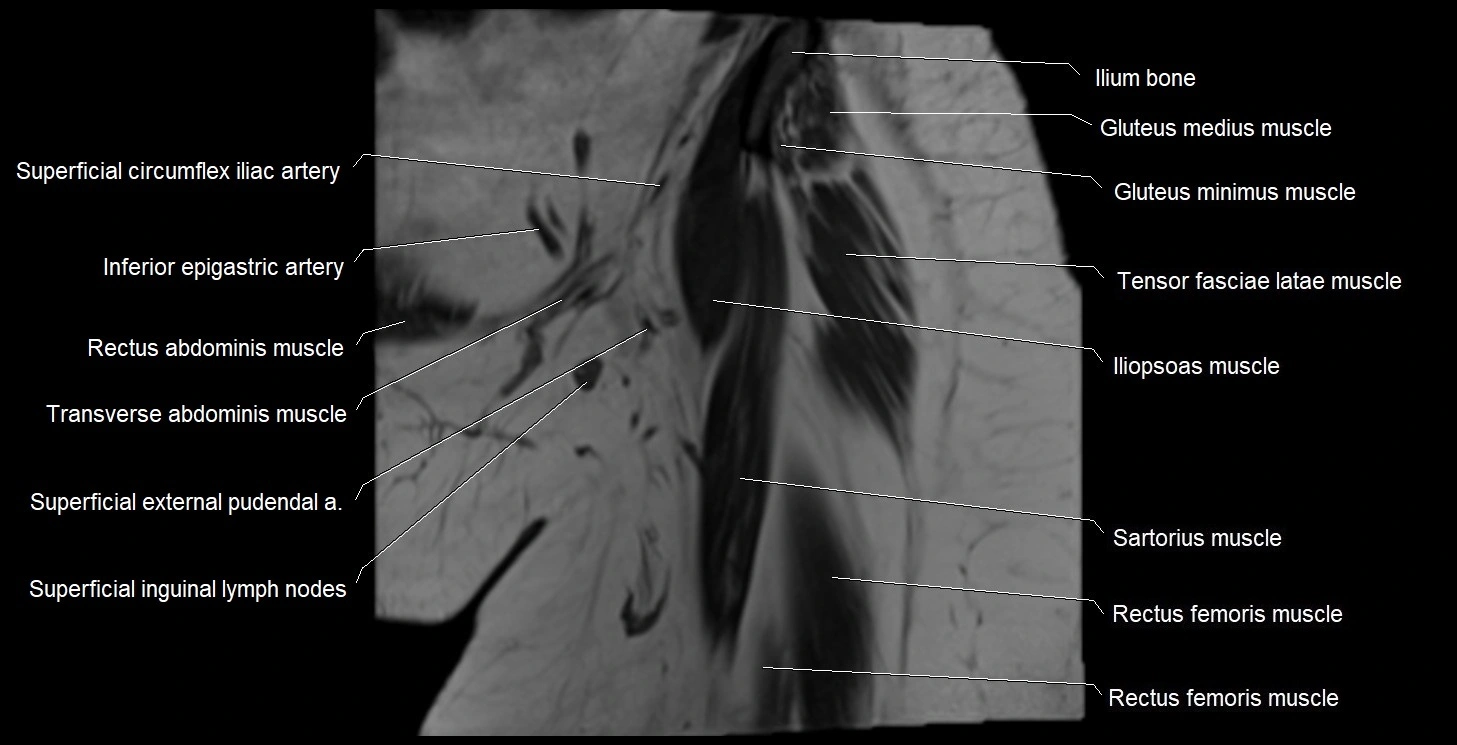

- Gluteus minimus muscle

- Iliopsoas muscle

- Inferior epigastric artery

- Inguinal lymph nodes

- Rectus femoris muscle

- Sartorius muscle

- Superficial circumflex iliac artery

- Superficial inguinal lymph nodes

- Tensor fasciae latae muscle